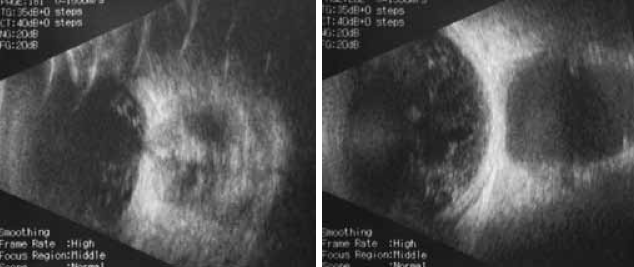

При обследовании в клинике выявлен выраженный правосторонний экзофтальм со смещением глаза книзу кнаружи, не дающий векам сомкнуться. Роговица уменьшена в размерах до 8 мм, мутная в оптической зоне. В пределах открытой глазной щели истончение роговицы ксеротического генеза. Колобома радужки на 6 часах (рис. 4, 5). Рефлекс с глазного дна резко ослаблен из-за состояния роговицы, неравномерно розовый с желтыми участками. Внутриглазное давление (пальпаторно) нормальное.

Рис. 4. Внешний вид ребенка М. при поступлении в офтальмологическое отделение

Рис. 5. Ксеротическая язва роговицы правого глаза ребенка М.

На левом глазу пациента выявлены колобома сосудистой оболочки и зрительного нерва.